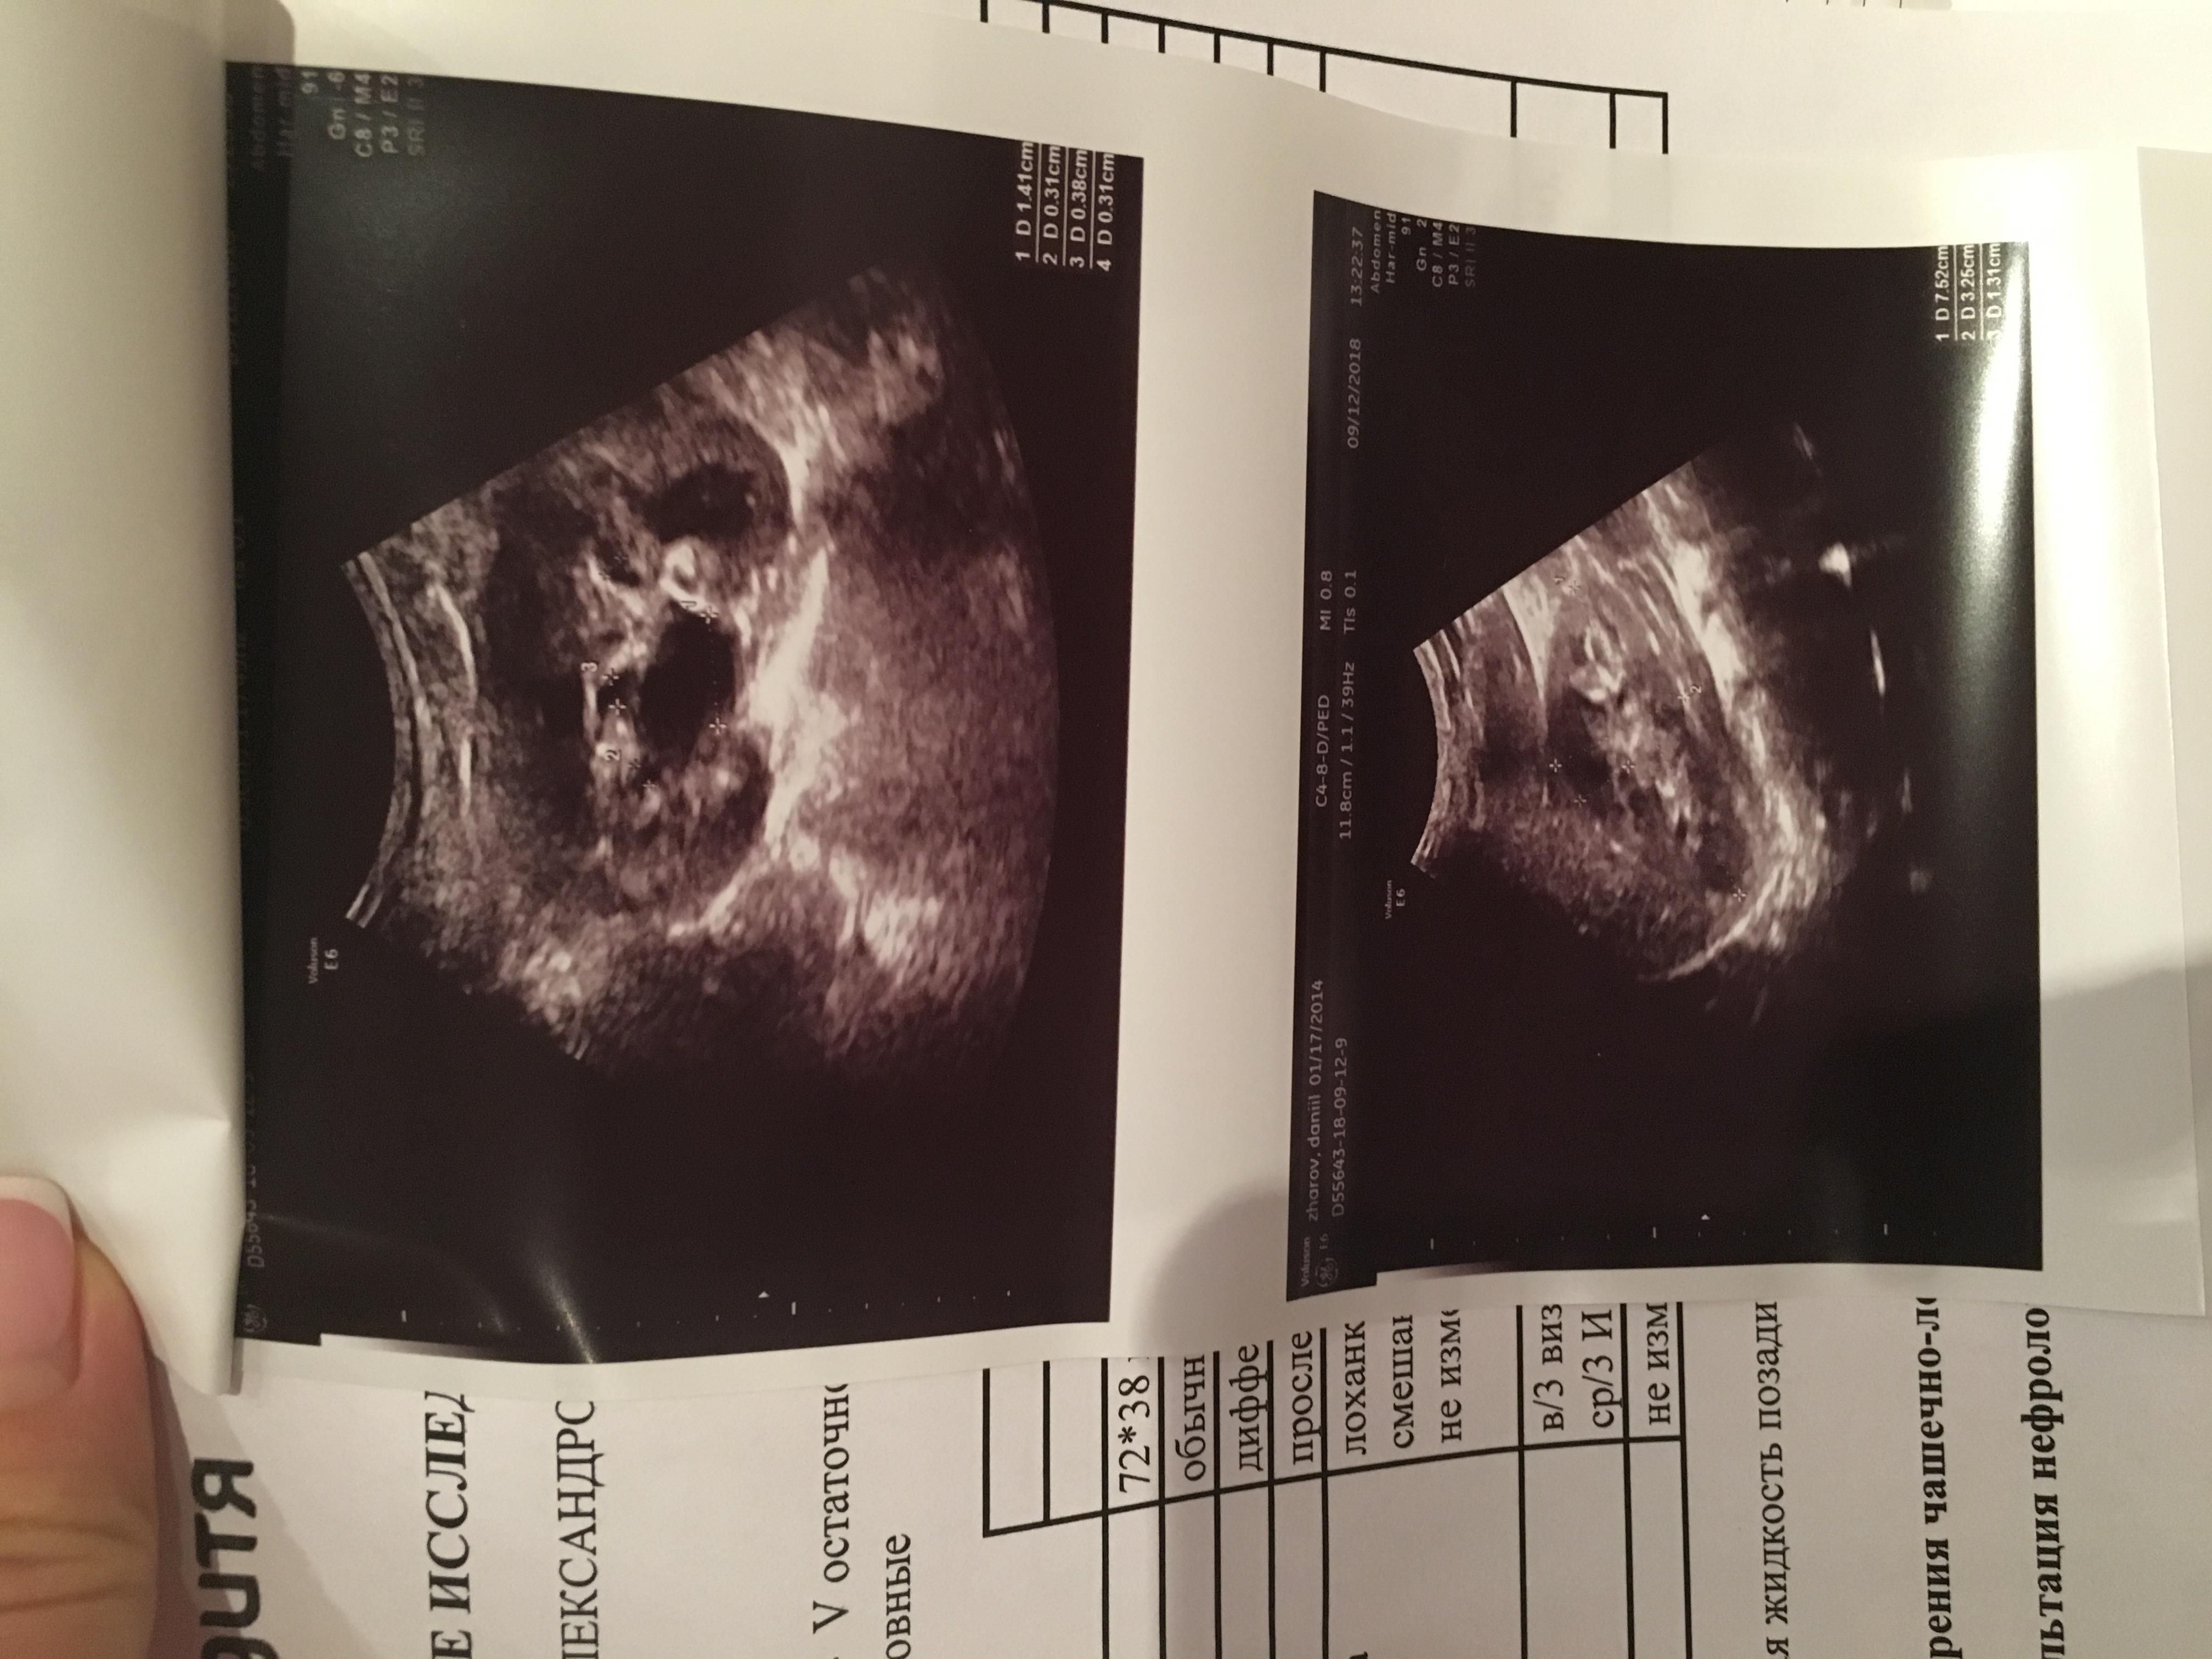

при рождении и в 3 месяца почки были без изменений.В 1 год 1 месяц после ОРВИ у ребенка появился запах ацетона в моче, в бак.посебе протеус мирабилюс 10*6 степени, лейкоциты в оам-30,УЗИ-левая лоханка 5 мм,все остальные показатели в норме,пропили антибиотик зиннат, далее фурагин,канефрон,согласно рекомендациям нефролога. Контроль УЗИ после лечения-норма,оам-идеальный.В 2 года узи -левая лоханка 8 мм,правая 8, чашечки не уанличены,остальные показатели в норме.В 3 года узи: лоханки левая 5 мм,правая 4 мм,все остальные показатели в норме,оам-норма.В 3.10 мес(ноябрь 17г)ребенку поставлен диагноз-нейрогенный мочевой пузырь(узи,урофлоуметрия),оксалурия( в Ноябре 17г. (до этого в октябре 17г. перенес орви с темп.40),Темп 38.5 без признаков орви,мутная моча,частое мочеиспускание малыми порциями,осадок в горшке кирпичного цвета, по оам все показатель в норме, кроме солей(ураты,оксалаты)в большом кол-е). Согласно результатам узи левая лоханка 22 мм,остальные показатели в норме.Лечились у нефролога,поэтапно принимали препараты для почек(фурагин,канефрон,трава пол-пола,донат магния,мин.вода фьюджи,витамин в6,веторон), для кишечника(эубикор крошка,кидз саше,лактофильтрум), диета 5 и питьевой режим 1.6 л в день,сахар по глюкометру 4.7.Вели дневник Мочеиспусканий в теч.4 дней,в среднем обьем выпитой жидкости составлял 1,5, обьем вырущенной 1.4.,мочился больше 12 раз в день.Мочеиспускание без затруднений. После лечения сделали узи,члс была в преднлах нормы, но диагностирован нейрогенный мочевой пузырь( пописал 250 мл, осталось 10 мл).анализы мочи -не придраться. Придерживаемся диеты 5 с февраля 18 г по сей день,выпиваем воды 1.6 л в день.22 августа прошли диспансеризацию и сделали для контроля узи почек/ доплер на высокочувствительном аппарате, результаты обследования меня мягко сказать огорошили- по узи чашечки расширены слева 5 мм(прежде расширений чашечек никогда не диагностировалось),лоханки слева 11 мм ,плюс в почках обнаружен песок, остальные показатели в норме,доплер-сосуды в норме.ОАМ-норма.Получается во время приема мочегонных препаратов, лоханки в норме(за исключением нейрогенного мочевого пузыря он имеет место быть),как только перестаем лечиться образуются соли .. хотя сидим на диете и пьем много воды. 4 сентября в ницрр сделали динамическую сцинтиграфию с микционной пробой, по результатам обследования функция почек не нарушена,но,слевой стороны обнаружен незначительный лоханочно-чашечный рефлюкс( результаты обследования, узи и пр.прилагаю).Какие наши дальнейшие действия? Складывается такое впечатление,что все это время мы бечили следствие заболевания,а не саму причину.. Заранее благодарна за ответ!